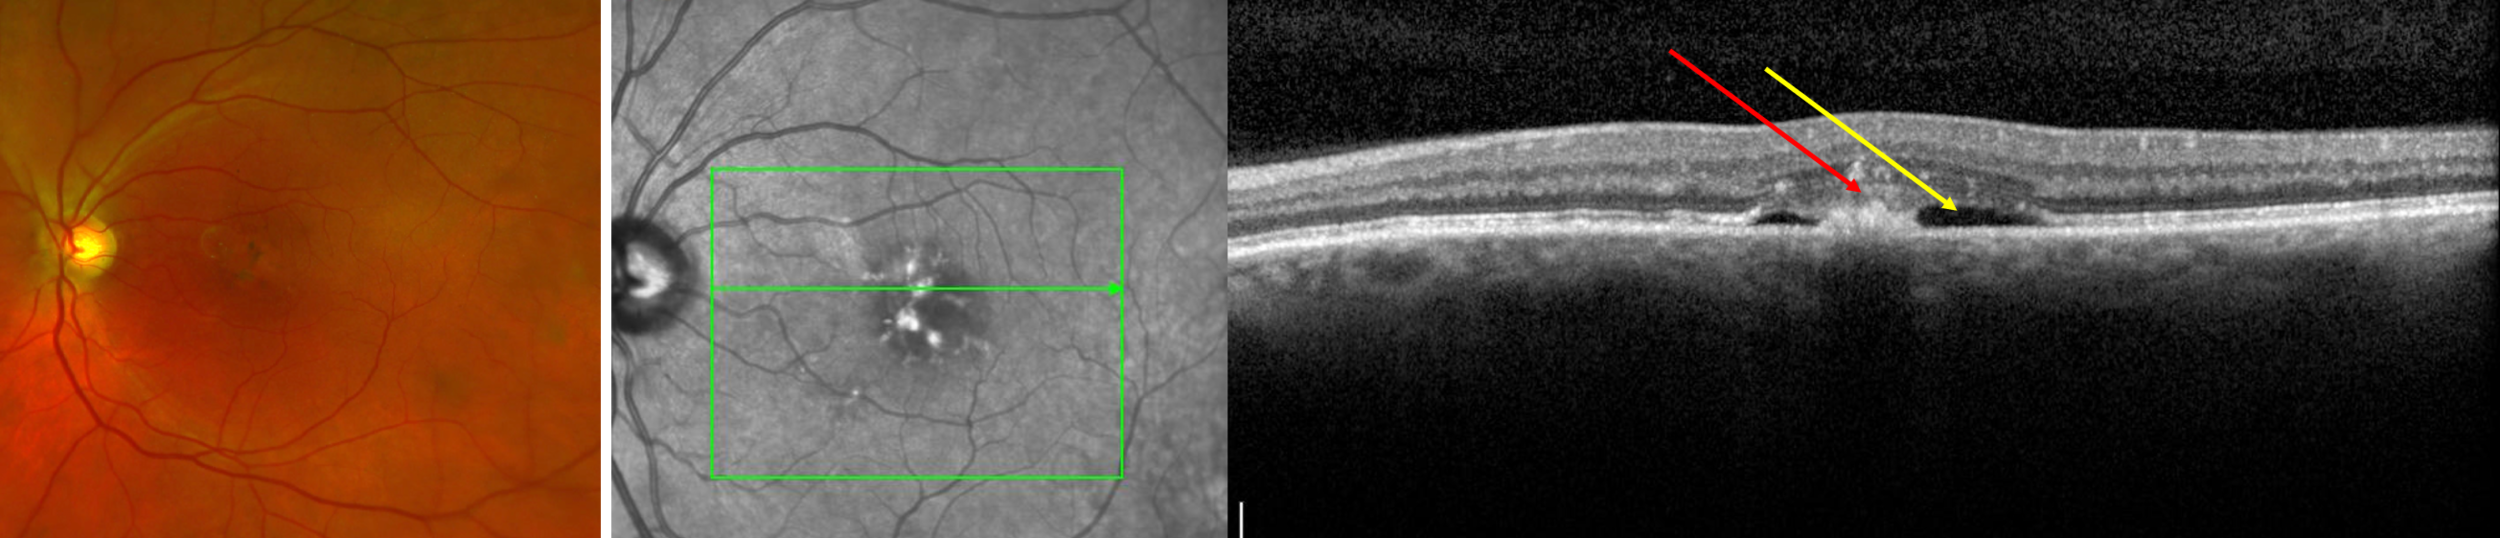

- Wet age-related macular degeneration (wet AMD, also known as exudative AMD)

- Wet AMD has all the features of dry AMD, plus:

- New blood vessels that grow under and/or into the retina. This abnormal blood vessel growth is called “choroidal neovascularization.”

- The abnormal blood vessels leak fluid or blood into the retina, thus “wet” AMD

- Vision decrease may occur gradually or it can occur suddenly, with potentially vision loss

- Dilated retinal examination

- Optical coherence tomography (OCT) scan: painless photograph that provides a cross-sectional scan through the macula so that microscopic details of the macula can be discerned

- Fluorescein angiography

- A dye is injected into the arm, from which to travels through the blood to the eye.

- Photographs are taken of the eye which map out all the blood vessels and blood flow in the retina

- This test identifies areas of blood flow loss as well as areas of new blood vessel grown (neovascularization)